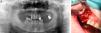

Hubo 7 pacientes en estadio 1 (37%) (fig. 1 a-b), 8 en estadio 2 (42%) (fig. 2a-b) y 4 en estadio 3 (21%) (fig. 2 c).

Los pacientes en estadio 3 fueron tratados en todos los casos con mandibulectomía segmentaria. Tres de ellos fueron reconstruidos con colgajo microquirúrgico de peroné (fig. 4 a-c), y uno con barra mandibular más cierre directo. Fueron tratados mediante secuestrectomía 7 pacientes, de los cuales 5 tenían estadio 2 y 2 estadio 1. Con desbridamiento local solo fue tratado un paciente que presentaba estadio 1. El tratamiento conservador se aplicó al resto de los pacientes en estadio 1 (4 pacientes) y a 3 pacientes del estadio 2.

Estadio 3. (4 casos). El paciente tratado con mandibulectomía segmentaria y barra de titanio presentó una infección a los 8 meses que obligó a retirarla. Tres meses después se volvió a fijar con otra barra, que no presentaba más complicaciones tras 24 meses. Los otros 3 pacientes tratados con mandibulectomía segmentaria y reconstrucción con colgajo de peroné evolucionaron satisfactoriamente. Dos de ellos fueron rehabilitados con implantes dentales 6 meses después. El otro usa prótesis removible. Ninguno ha registrado complicaciones al cabo de 12 meses.